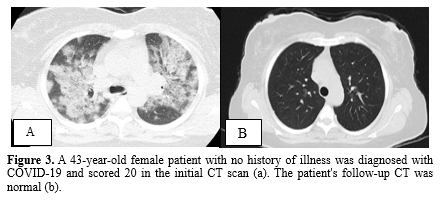

Mild fibrosis was observed in 21 individuals (70%) on the follow-up CT scans, while the remaining patients exhibited normal chest CT findings. The most common abnormalities observed were a fibrotic band (67%) and a fibrotic band with GGO (33%). No cases of pneumomediastinum or bronchiectasis were detected in any of the follow-up CT scans. Figures 2, 3, and 4 provide a visual comparison of baseline and follow-up chest CT scans for three patients.